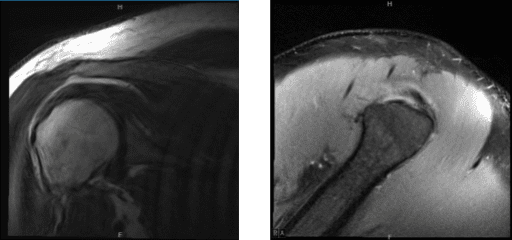

MRI showed an impression as follows: High-grade partial-thickness articular sided tear of the infraspinatus tendon. Moderate supraspinatus tendinosis. Mild long head biceps tendinosis. Mild AC arthrosis. Moderate degenerative tearing of the superior labrum. We discussed treatment options and the patient opted for surgical management.

MRI of right shoulder